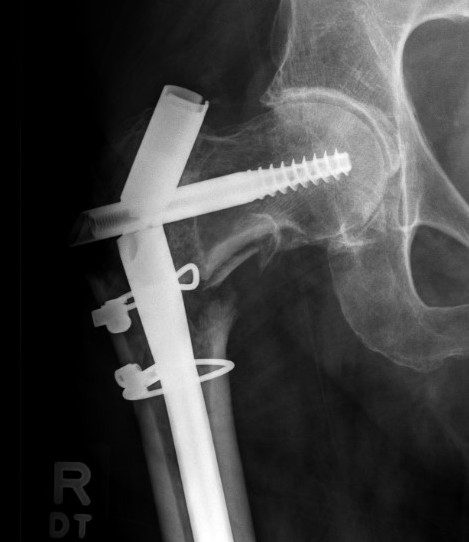

1. Short transverse fracture

- clamps on proximal and distal fragments and hold reduced

- consider unicortical small plate to hold reduction

- consider blocking screws